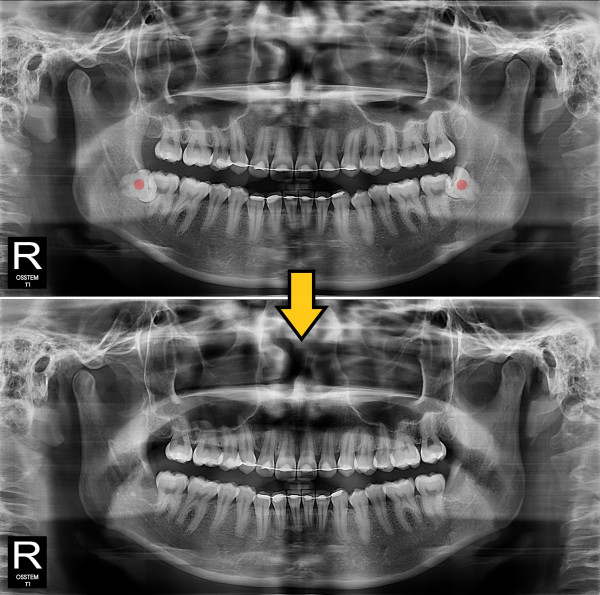

사랑니발치 완전 매복 사랑니

826e40416d712e6cd444a78bde93df4b_1767856842_6172.jpg